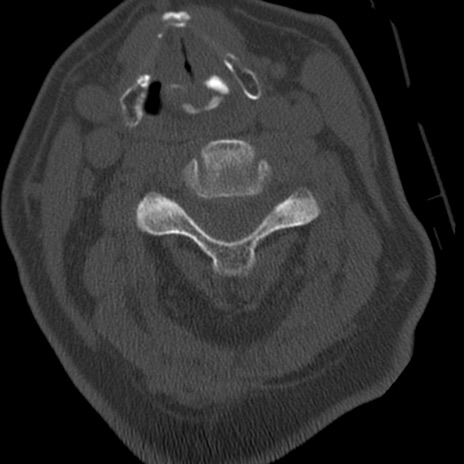

症例50 頚椎CT(横断像)

矢状断像